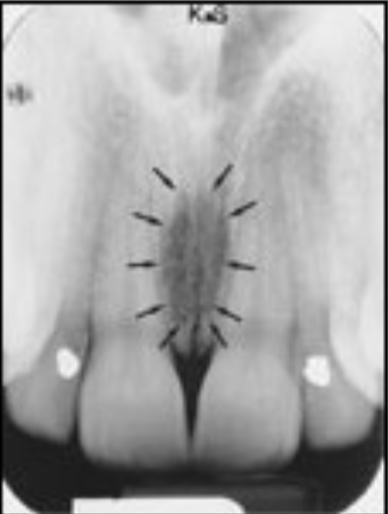

what does this show

beam hardening